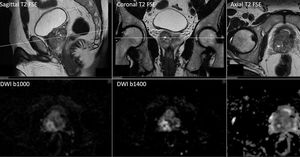

Multiparametric MR Imaging of the prostate gland, based on high-resolution anatomical T2-w FSE acquisitions in three imaging planes, DWI with b50 (not shown here), b1000, b1400 and ADC map and DCE PWI (not shown here). DWI can clearly demonstrates the pathology with high sensitivity. Patient will undergo U/S guided biopsy. Images courtesy of Christos Tsiotsios.